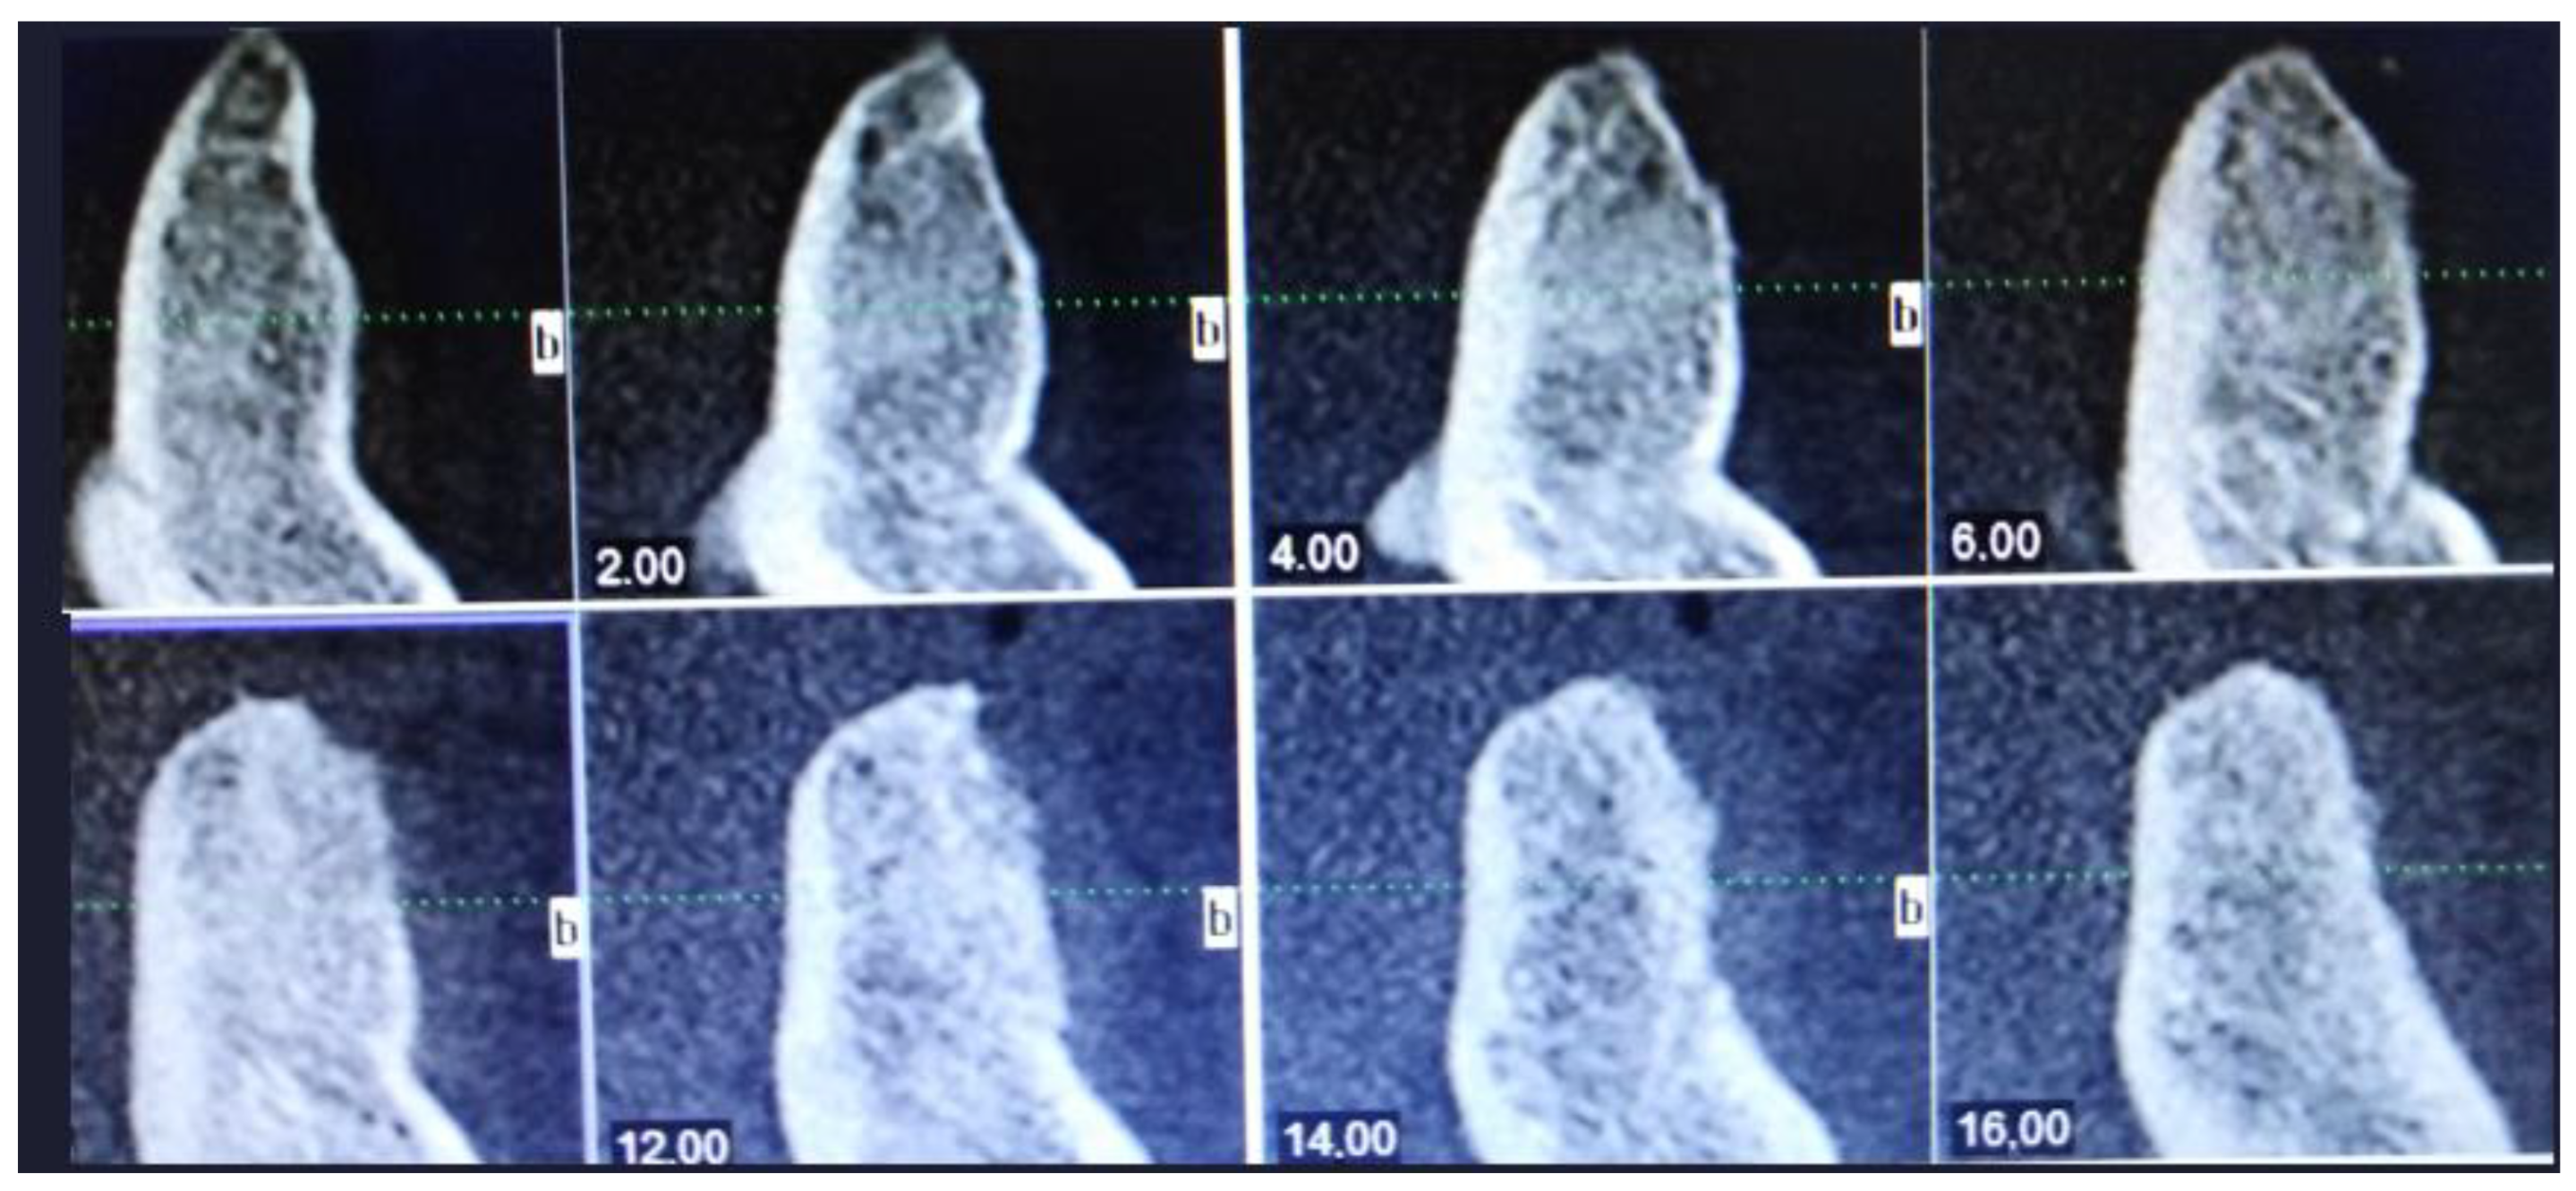

The final HP examination revealed the presence of OKC. During routine check-ups the healing was good, the swelling was normal, and sutures were removed after 14 days. The follow-up examination was made four years after surgery. During the consultation, the clinical and radiological appearance of the bone and surrounding soft tissue was normal. Proper bone healing was achieved clinically and on routine CBCT (Figure 7, Figure 8 and Figure 9). Four dental implants, Neodent 3.5/8 mm and 4.0/10 mm (Straumann Group, Arlington, TX, USA), were scheduled. The patient was supposed to be scheduled for FMT (full mouth therapy) and dental implant placement, however, because of the SARS-CoV-2 pandemic, the patient used partial acrylic removable dentures for over two years. By that time, the patient got used to the dentures and decided to reject the proposed further implant placement (Figure 10, Figure 11 and Figure 12).

Figure 4. The scope of cystic lesion in CBCT.

Figure 10. The scope of regenerated bone in CBCT after four years.